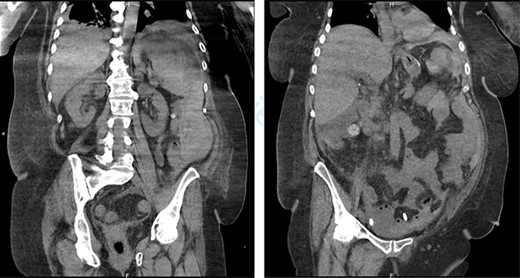

First, we embolized the splenic artery with coils (Fig. 3). The patient was getting well at intensive unit care, but few hours after embolization, she was shocked again.